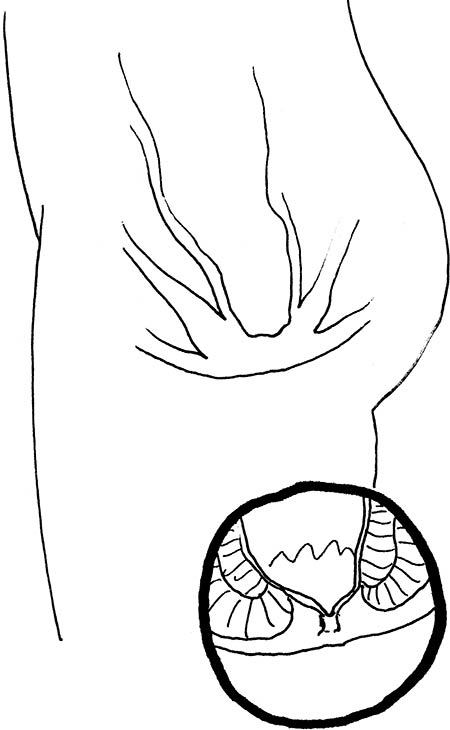

Проверять детские анусы следует примерно так.

Вопрос № 2. Нормально ли выглядит кожа вокруг ануса?

Этот вопрос требует представления о том, как обычно выглядит кожа вокруг ануса вашего ребенка.

Всем родителям, которые читают эту книгу, стоит прямо сейчас взять своего ребенка и попросить его продемонстрировать анус, если он до сих пор не сделал этого. Не откладывайте: вам необходимо точно знать, как выглядит анус вашего ребенка в нормальном состоянии. Как иначе вы сможете подметить свежее заболевание в тот день, когда чадо станет активно чесаться? Это был риторический вопрос, но если вы придумаете на него творческий ответ, вы получите очко за хорошее воображение. Если у вас под рукой однояйцевые близнецы, вам повезло: вы всегда сможете безошибочно определить, когда одному из анусов нездоровится.